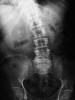

Escoliosis. Espondilolistesis.